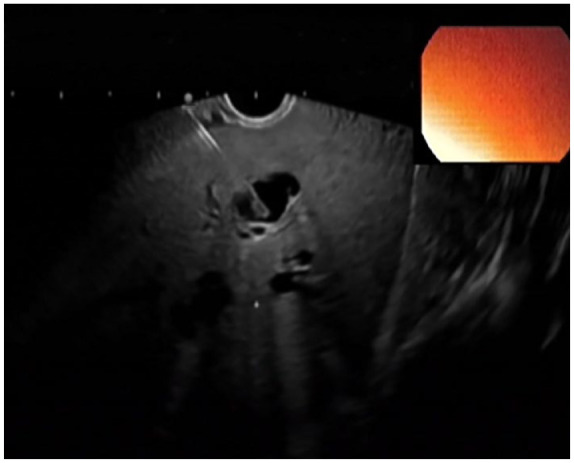

After failed biliary cannulation via standard endoscopic retrograde cholangiography approach, endoscopic-ultrasound-based rendezvous-endoscopic retrograde cholangiography (EUS-RV-ERC) is a valid alternative. One of the challenging factors in this setting is the management of the guidewire. Here, we propose a method, where a slim endoscope is used to stabilize the guidewire and optimize wire manipulation in a patient who underwent EUS-RV-ERC via a transgastric approach. This was executed in a patient suffering from severe alcoholic pancreatitis presented with a severely narrowed duodenum due to extrinsic compression and inflammation in the setting of cholangitis Tokyo Grade III.

Abstract Image